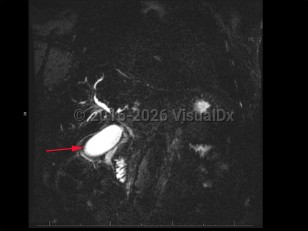

Cholangiocarcinoma refers to biliary tree malignancies, primarily adenocarcinomas, of epithelial cell origin. They are typically categorized as intrahepatic, perihilar, or distal.

Cholangiocarcinoma